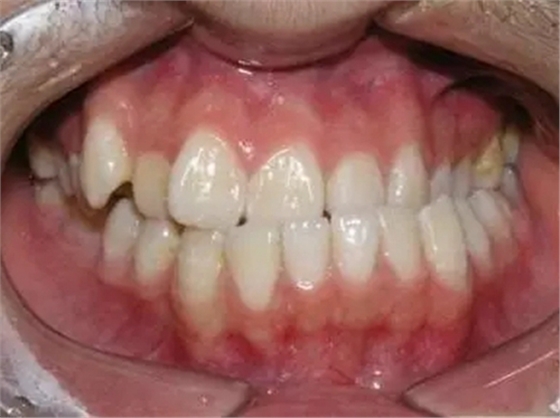

1、錯合畸形、咬合關(guān)系紊亂

由于反復(fù)向一側(cè)運動,使下前牙的正中線向一側(cè)錯位從而導(dǎo)致后邊的牙齒形成刃對刃、尖對尖的咬合,甚至反咬合(下牙包上牙)。